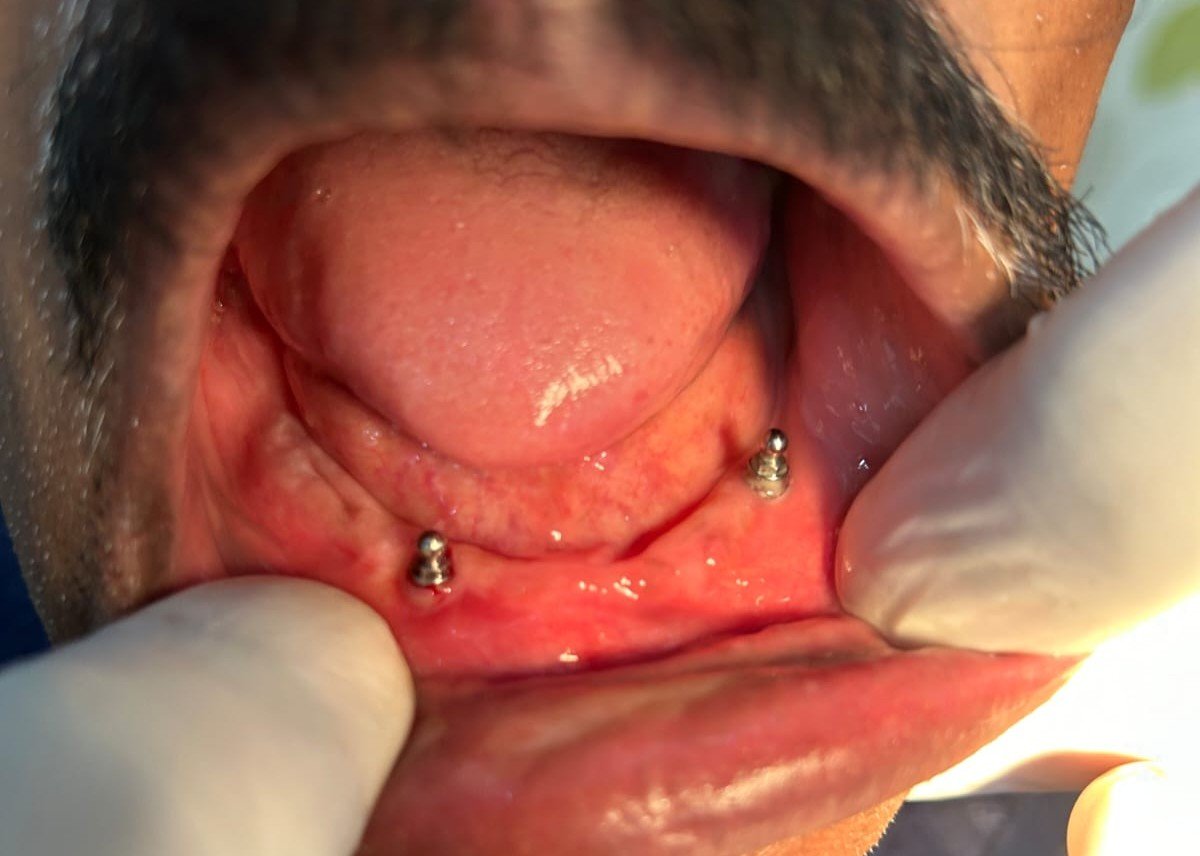

Dental implants are a modern and reliable solution for replacing missing teeth. They are designed to restore both the appearance and function of natural teeth. A dental implant consists of a small titanium post that is surgically placed into the jawbone, where it acts as an artificial root for the missing tooth. This procedure helps provide a stable and long-lasting foundation for the replacement tooth.

Dental implants are commonly recommended for patients who have lost one or more teeth due to injury, decay, or gum disease. Once the implant is placed into the jawbone, it gradually integrates with the bone through a natural healing process, providing strong support for the artificial tooth. After the healing period, a dental crown is attached to the implant to restore the appearance and function of the natural tooth. One of the major advantages of dental implants is that they help preserve the jawbone and prevent bone loss that can occur after tooth loss. Unlike removable dentures, implants are fixed in place and function similarly to natural teeth, allowing patients to chew, speak, and smile with confidence. With proper oral hygiene and regular dental check-ups, dental implants can last for many years. This treatment provides a durable and effective solution for restoring missing teeth and improving overall oral health and facial aesthetics.